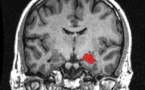

El hipocampo de hombres y mujeres es igual de grande - 02/11/2015

Una investigación realizada en EE.UU. mediante resonancia magnética desmiente la creencia generalizada de que el hipocampo, una parte crucial del cerebro que consolida nuevos recuerdos y ayuda a conectar las emociones con los sentidos, es mayor en las mujeres que en los hombres.

Aprender a navegar espacialmente produce cambios en el cerebro - 28/10/2015

Científicos de Estados Unidos han demostrado que el aprendizaje para navegar espacialmente produce cambios en el cerebro, en especial en el hipocampo. Ya se sabía, por ejemplo, que los taxistas de Londres, tenían un alargamiento en esta región, pero no se sabía cuál era la causa y cuál la consecuencia.